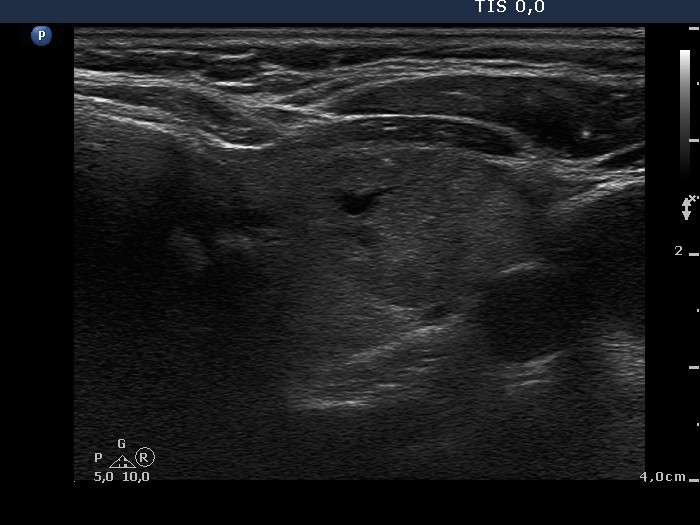

Ultrasonography. The thyroid was composed of multiple nodules with different echogenicities. There was a small hypoechogenic lesion above the right lobe.

Cytology was performed from the lesion above the thyroid and resulted in benign colloid goiter.

Histopathology disclosed benign hyperplastic nodules even in the case of the lesion above the right lobe which was located outside the thyroid.